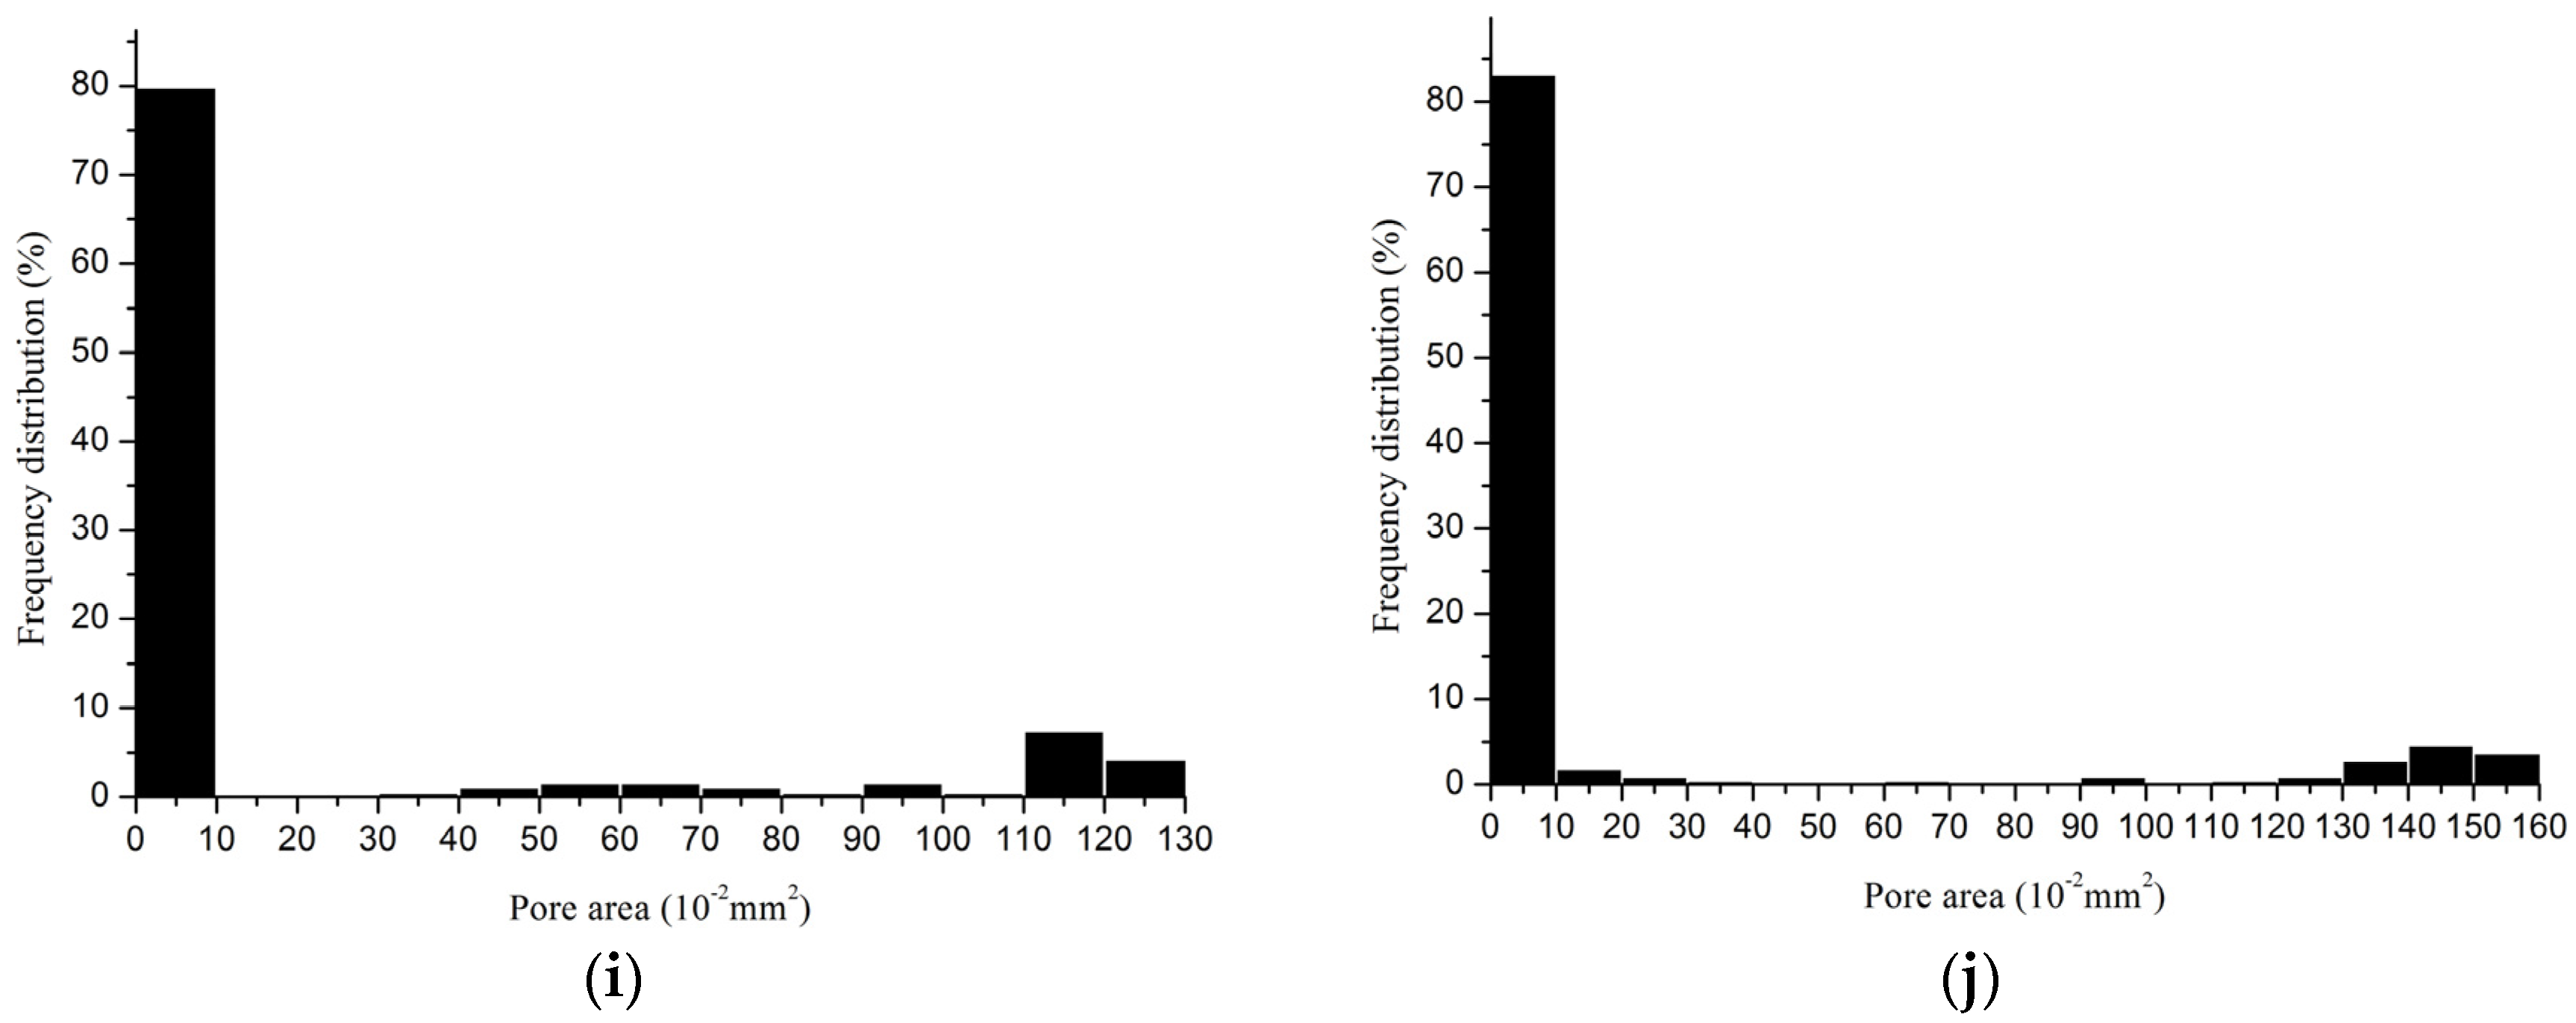

2.2.3. Porosity

| Device | Minimum Pore Size (mm2) | Maximum Pore Size (mm2) | Porosity (%) | Porosity I * (%) |

|---|---|---|---|---|

| 1 | 0.0007 | 0.6500 | 42.6 | 0 |

| 2 | 0.0018 | 0.8700 | 61.7 | 5.9 |

| 3 | 0.0040 | 0.5899 | 40.5 | 0 |

| 6-1 | 0.0065 | 0.9827 | 44.4 | 5.1 |

| 6-2 | 0.0096 | 0.7300 | 42.1 | 0 |

| 7 | 0.0012 | 0.3916 | 37.3 | 0 |

| Device | Minimum Pore Size (mm2) | Maximum Pore Size (mm2) | Porosity (%) | Porosity I * (%) |

|---|---|---|---|---|

| 4 | 0.0042 | 2.400 | 64.2 | 54.7 |

| 5 | 0.0044 | 1.900 | 58.2 | 30.8 |

| 8 | 0.0052 | 1.2517 | 60.1 | 46.2 |

| 9 | 0.0013 | 1.5776 | 69.2 | 60.1 |

3.2. Pore Characteristics

3.4. Which Method Could Be Most Effective in Characterizing the Pore Size of Hernia Prostheses?